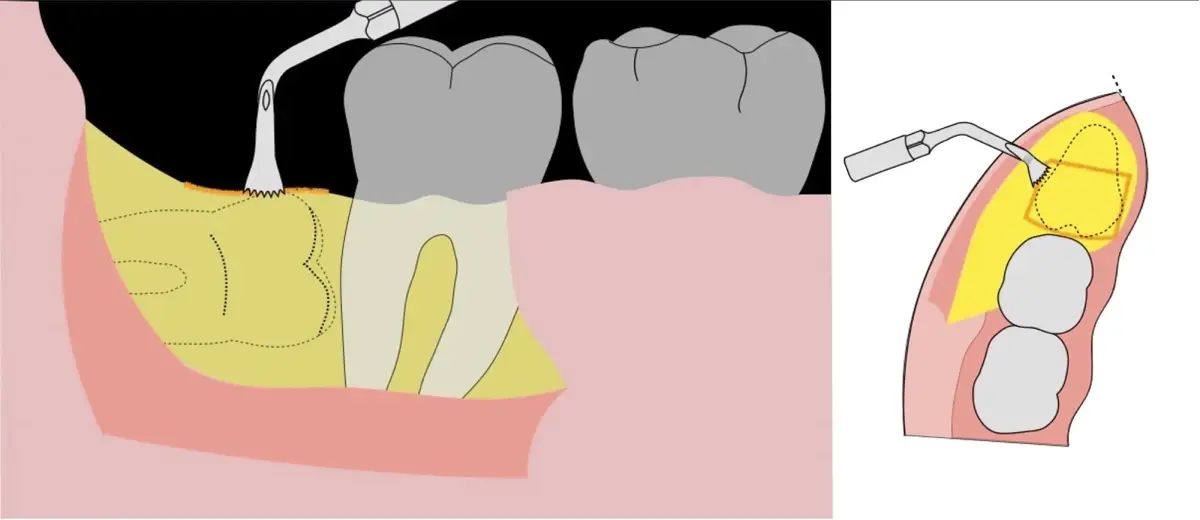

Figura 11. Avulsión del remanente radicular de la tercera molar.

Figura 12. Eliminación del capuchón pericoronario y verificación del lecho óseo posterior a la exodoncia.

Figura 13. Afrontamiento del colgajo y sutura.